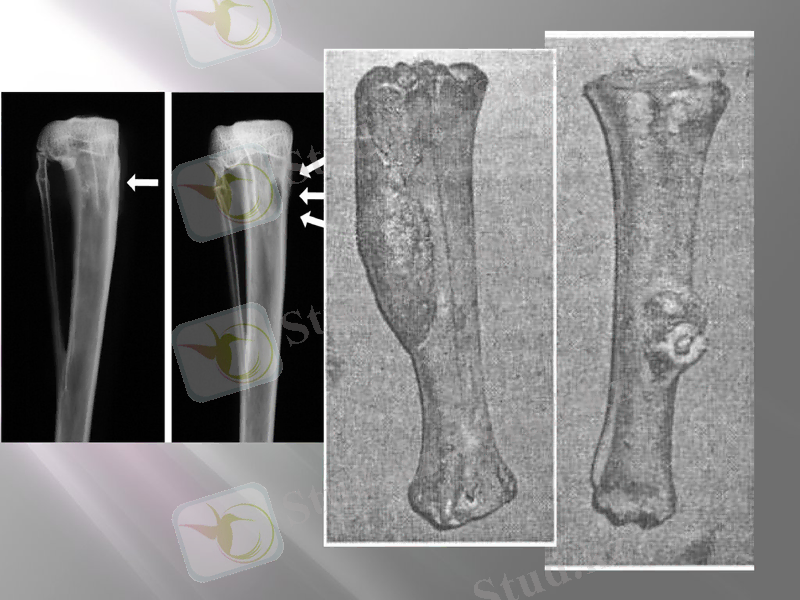

Оссифирленушi периостит. Сүйек ұлпасының өсуi, көбейуi қабынған сүйек беттерiнен басталады. Фиброзды периоститте сүйек сыртқы қабығының қабынуы iшiнен де, сыртынан да басталады. Сүйек үстінiң сыртқы және iшкi қабынулары, негiзiнен механикалық фактордан iшкi қабынулардан болады (зақымданулар, сынықтар, сүйектiң жарылулары, буынның дистрозиясы, көбiне байламдардың сүйекке бекiтiлген жерiндегi жыртылуы) және қабыну процестерiнiң жақын орналасқан ұлпалардағы абцесстен, флегмонадан, жаралардың асқынуынан болады. Оссифицирленген периоститке мал аяқтарының маймағы, ауыр жұмыстар қатты әсерiн тигiзiп, ет, сiңiр, байлам ұлпаларының зақымдануына септiгiн тигiзедi.

Клиникалық белгiлерi. Сүйектiң зақымдалған аймағын терең пальпациялағанда шеттерi шектелген, тығыз, бетi тегiс, температурасы жоқ қызарған iсiнулер тiркеледi. Периостит бетiндегi терi жеңiл қозғалады. Фиброзды периоститте қан, лифа тамырларының, жүйке жүйелерiнiң, сiңiрлердiң, буындардың шоғырланған тұсында қатты ауырсыну байқалады.

Токсикалық оссифирленушi периостит қабыну белгiлерi жоқ сүйек үстіндегi пролиферативтi процестерге жатады. Бiрнеше оссифирленушi түтiкшелi сүйектердiң қатпарлануымен сипатталады.

Клиникалық белгiлерi. Пальпациялағанда көптеген гиперостоздар анықталады. Иттерде фалангалы сүйектерiнде, иық және тiзе сүйегінiң эпифидерзiнде дамиды.

Ренгенографияның көмегiмен диагнозы анықталады.